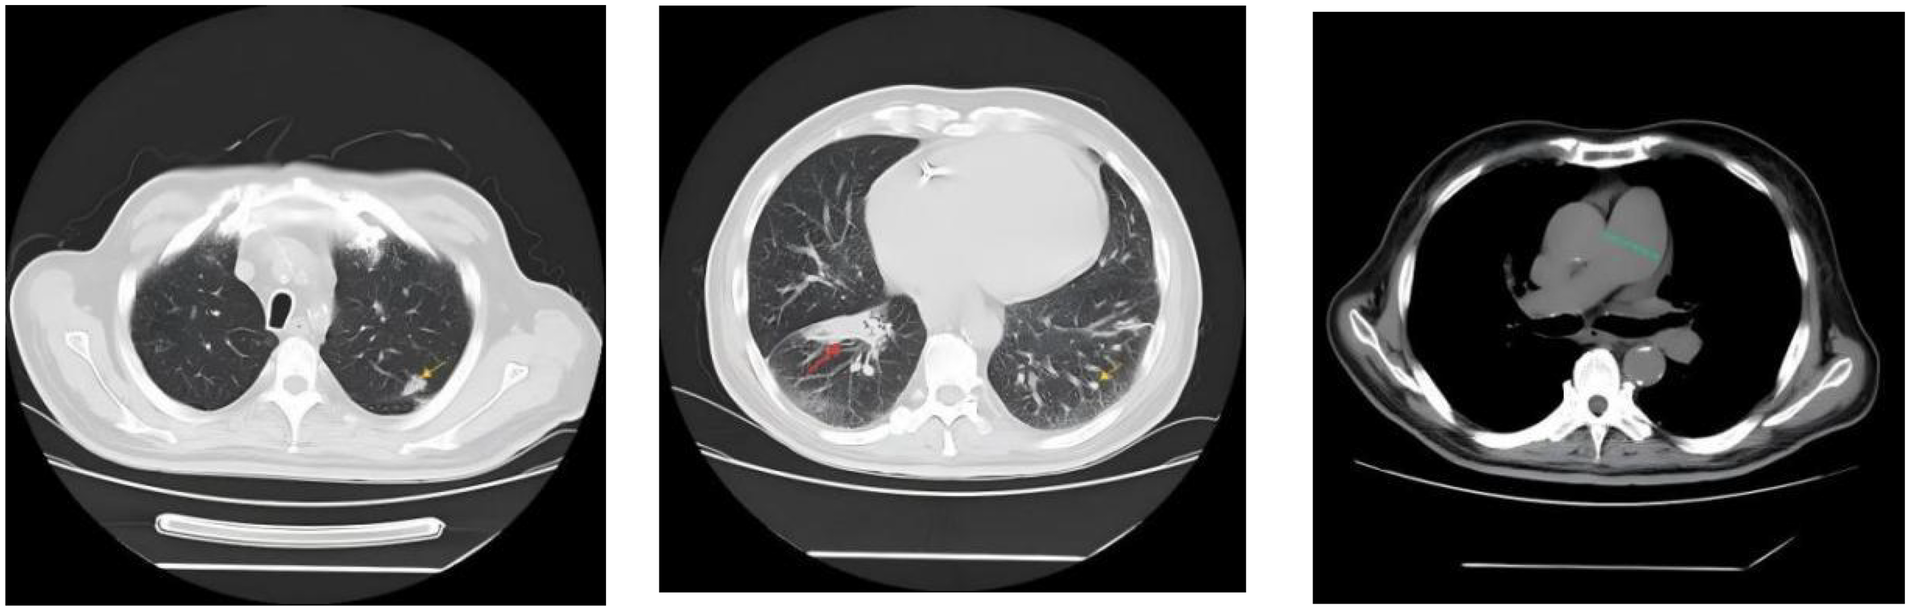

Femoral arterial blood gas analysis showed PaO2 49.7ā mm Hg, PaCO2 28.4ā mm Hg, oxygen saturation 86.6%. Venous blood tests showed brain natriuretic peptide (BNP) 1,043ā pg/mL (Reference range, 0ā100ā pg/mL), D-dimer 0.63ā µg/mL (Reference range, 0ā0.5ā µg/mL), squamous cell carcinoma antigen 6.6ā ng/mL (Reference range, 0ā1.5ā ng/mL). No significant abnormalities were observed in liver and kidney function, thyroid function, complete blood count, urinalysis, stool routine, hepatitis B serology, human immunodeficiency virus antibody, hepatitis C virus antibody, autoimmune disease-related antibodies. Electrocardiogram showed sinus rhythm, first-degree atrioventricular block, right axis deviation (FigureĀ 1). Chest computed tomography (CT) demonstrated a mass lesion in the right lower lobe of the lung (maximum cross-section: 4.7āĆā2.1ā cm), scattered nodules (2ā5ā mm in diameter) bilaterally, along with dilatation of the pulmonary artery (with a diameter of 39.52ā mm) (FigureĀ 2). CT pulmonary angiography revealed no significant abnormalities in the main pulmonary artery, left and right pulmonary arteries, or their branches. Lung perfusion Single-Photon Emission Computed Tomography-CT (SPECT-CT) showed no definite signs of pulmonary embolism. TTE demonstrated an enlarged RV causing compression of the left ventricle (LV), resulting in a D-shaped deformation of the LV. Severe impairment of RV systolic function was observed, with a tricuspid annular plane systolic excursion (TAPSE) of 12.2ā mm and an Sā² wave of 7.9ā cm/s at the RV free wall. Additional findings included moderate tricuspid regurgitation, severe PH (PASP, 84ā mm Hg), dilated inferior vena cava, and abnormal respiratory collapse (FigureĀ 3). RHC revealed PAP of 87/40ā mm Hg (mPAP 55ā mm Hg), pulmonary artery wedge pressure (PAWP) of 8ā mm Hg, PVR of 18.4 Wood units, cardiac output of 2.55ā L/min, cardiac index of 1.5ā L/min/m2. The findings are consistent with precapillary PH, supporting the diagnosis of PAH, classified as high risk. Pulmonary angiography showed no significant filling defects or abnormalities in the opacification of both pulmonary arteries.

FigureĀ 2

Chest CT demonstrated a mass lesion in the right lower lobe of the lung (maximum cross-section: 4.7āĆā2.1ā cm, indicated by the red arrow), scattered nodules (2ā5ā mm in diameter) bilaterally (indicated by the yellow arrow), along with dilatation of the pulmonary artery (with a diameter of 39.52ā mm, indicated by the green dashed line).

The current examination findings support the diagnosis of PAH (Group 1 PH) in this patient. Given that the PAWP measured by RHC was less than 15ā mm Hg, combined with TTE findings characterized by RV enlargement and LV compression with reduced volume, Group 2 PH was ruled out. Although the chest CT scan revealed a local mass (maximum cross-section: 4.7āĆā2.1 cm, see FigureĀ 2), its size was significantly reduced compared with the initial detection of the tumor 3 years ago (with a maximum cross-section of 7.5āĆā4.3ā cm at that time, and no signs of PH were noted on TTE). Therefore, PH secondary to the tumor was excluded. No evidence of emphysema, chronic obstructive pulmonary disease, or pulmonary fibrosis was identified on the CT scan, thus ruling out Group 3 PH. Pulmonary function tests demonstrated generally normal pulmonary ventilation function, normal respiratory reserve function, normal lung volume, and roughly normal residual lung volume, along with severe impairment of pulmonary diffusing capacity. These findings further confirm that the patient does not have Group 3 PH but is consistent with the manifestations of PAH. Additionally, neither pulmonary perfusion SPECT-CT nor pulmonary angiography showed signs of pulmonary artery obstruction, leading to the exclusion of Group 4 PH.